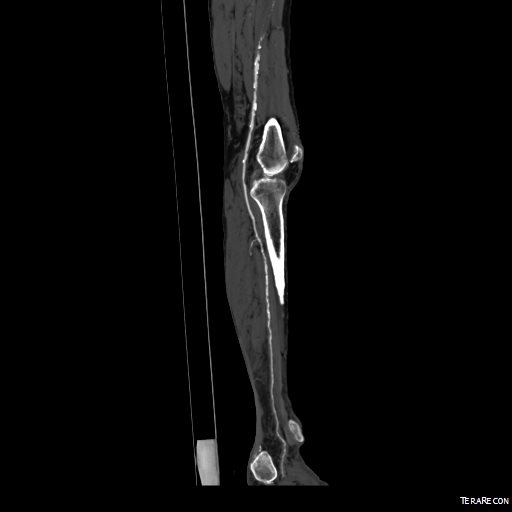

CTA (pictured above and below) showed a 5.1cm infrarenal AAA with an hourglass shaped neck with moderate atherosclerosis in the neck, an occluded left common iliac artery with external iliac artery reconstitution via internal iliac artery collaterals, and a right external iliac artery occlusion with common femoral artery reconstitution. There was calcified right common femoral artery plaque.

This patient presents with lifestyle limiting claudication and an absent right femoral pulse. ABI is moderately reduced on the right to 0.57, and he had no rest pain. CTA at our clinic revealed an occluded EIA bracketed by severely calcified and nearly occlusive plaque of the common iliac artery (CIA) and common femoral artery (CFA).

CTA showed that he had an occluded SFA with above knee reconstitute, but also had only single vessel runoff to the foot via a heavily diseased posterior tibial artery that had serial mild to moderate stenoses.